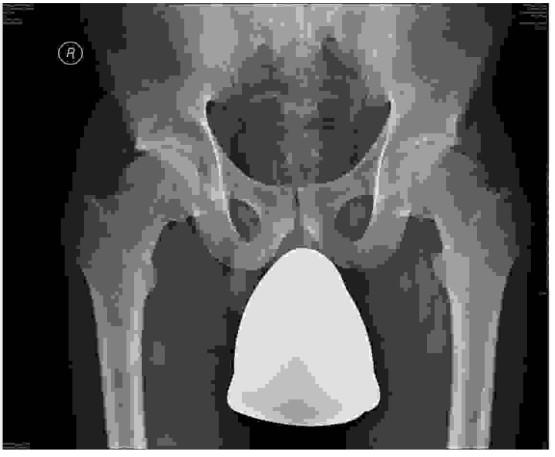

Poniższy radiogram stawów biodrowych w projekcji AP przedstawia: